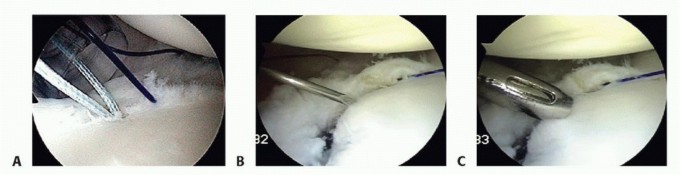

Tissue Mobilization and Glenoid Preparation

There is an old orthopedic adage: "If it doesn't bleed, it doesn't heal." The fundamental error in novice Bankart repairs is inadequate tissue mobilization. The labrum and capsule are often scarred medially down the glenoid neck, a classic ALPSA variant. Using an arthroscopic elevator, rasp, or radiofrequency ablation wand, the capsulolabral complex must be aggressively elevated off the anterior glenoid neck.

Image

This release must extend inferiorly past the 6 o'clock position (often requiring a switch of the viewing portal to the anterosuperior portal for adequate visualization) and medially until the red muscle belly of the subscapularis is clearly visualized. The tissue must "float" freely, allowing it to be shifted superiorly and laterally onto the glenoid face without any resting tension.

Once mobilized, the anterior glenoid rim is meticulously decorticated using a motorized burr or aggressive rasp. The goal is to remove the eburnated, sclerotic bone and create a bleeding, cancellous bone bed. This optimizes the biological healing environment, allowing the shifted capsulolabral complex to integrate solidly with the osseous glenoid.